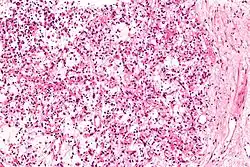

| Micrograph of an inflammatory myofibroblastic tumour of the kidney. Kidney biopsy. H&E stain. | |

Histopathologic examination of the tumors in IMT generally reveals myofibroblastic spindle cell sheets in a myxoid background (i.e. a background matrix containing gelatinous mucopolysaccharides and non-sulfated glycosaminoglycans); the matrix also contains inflammatory cells, particularly plasma cells and lymphocytes occasionally mixed with eosinophils and neutrophils. The epithelioid inflammatory myofibroblastic sarcoma subtype of IMT shows sheets of epithelioid to round cells within a myxoid (i.e. appears blue or purple compared to the normal red appearance of connective tissue when appropriately H&E stained and examined under the microscope), collagenous, or mixed myxoid-collagenous matrix, <5% spindle cells, and an inflammatory cell infiltrate that in most cases consists predominantly of neutrophils or, less often, small lymphocytes or eosinophils; plasma cells occur in only a minority of EIMS cases. The neoplastic cells in the tumors of 50% to 60% of IMT cases[2] and 100% of EIMS cases[3] express an ALK fusion protein. Other genetic abnormalities occur in these cells. Testing for the presence of the ALK fusion protein and other genetic abnormalities (see next section) can help diagnose IMT.[31]